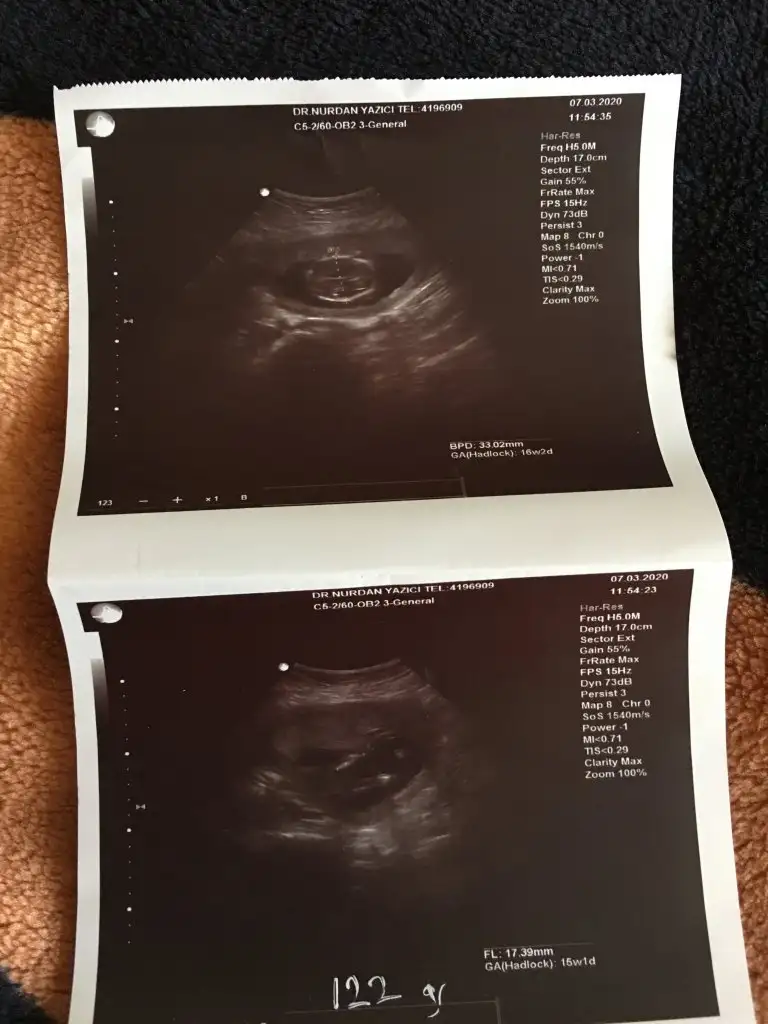

16 degil 11 -12 yada 13 haftalar olmalı dr söylemedimi sanki erkek gibi ama dediğim haftalara tahmin ediyorum

Kız sanki emin olamadım başka usgde paylaşınKızlar tahminde bulunabilirmisiniz ikiz bebekler 12 hafta 1 gunlikler

Bu kadar usg görüntüleri var malesefKız sanki emin olamadım başka usgde paylaşınsagdaki kız gibi digeri hiç görünmüyor

Tek yumurta ikizimi sanki ikiside kız tekrar usg olursa paylaşırsınız 13 haftada olurBu kadar usg görüntüleri var malesef![]()